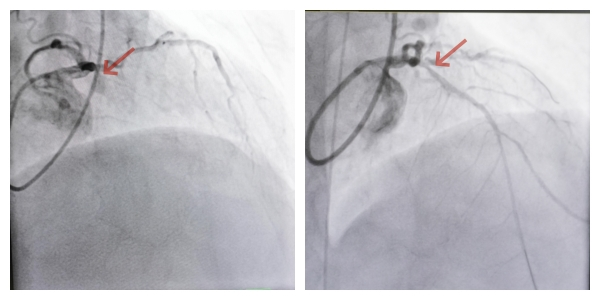

术前血管闭塞(左),术后血管开通(右)。

医疗团队决定采用分步治疗方案:先以药物球囊开通堵塞血管,待血流恢复、血管逐渐恢复正常直径后,再评估后续治疗。12月23日,在IABP(主动脉内球囊反搏技术)辅助下,郭卉为血压不稳、心功能不佳的梁先生施行手术,历时40分钟成功开通血管。术后次日,梁先生即转回普通病房,现已出院。

今年12月初,梁先生开始出现短暂胸闷,未予重视。到12月中旬,已发展到轻微活动就胸闷,遂紧急就医。检查显示,其心脏三根主要血管均狭窄,其中前降支中段100%堵塞,被确诊为“陈旧性前壁心肌梗死”,还伴有心脏扩大、室壁瘤等并发症。